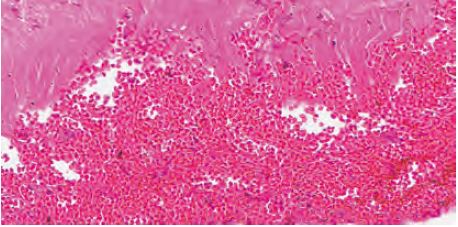

硬膜下血腫 subdural hematoma:SDH

外傷性SDHと非外傷性SDHがある。外傷性の多くの場合は,回転性の加速衝撃と非回転性の打撲により,架橋静脈(bridging vein)や皮質動脈・静脈(cortical artery/vein)が破綻して出血源となり,硬膜下に血腫を形成したものである。急性,亜急性,慢性がある。後述するが,虐待によって急性SDHが形成されることもある。

硬膜とくも膜の間は一般的にくも膜下腔といわれるが,実際には腔(スペース)はなく,疎な細胞成分で構成される硬膜境界細胞層(dural border cell layer:DBCL,図9-10)である。この層の主に硬膜側には硬膜静脈叢(dural venous plexus)があり,比較的軽微な脳への外力によっても破綻してSDHを形成することがあり,これが中村I型の発生メカニズムではないかという説もある。

慢性硬膜下血腫 chronic subdural hematoma:CSDH(図9-11)

CSDHは,たとえば老人が転倒するなどによる頭部外傷によって生じた硬膜下の血腫が慢性に経過したもので,血腫のまわりには結合組織が形成され,血腫自体が被包されたものである。CSDHは架橋静脈が破綻して生じるものが主体ではなく,前述したDBCLにおける小さな破壊病変から出血して次第に大きくなったものと考えられている。臨床的には外傷の既往が同定できない場合も多く,また,剖検によって初めて検出される程度のものも多い。このような場合は,硬膜がヘモジデリンによって黄褐色調になっていることが多い。

硬膜下血腫(SDH)の新しさ・古さの組織学的評価(図9-12〜17)

個々の症例によって違いはあると思われるが,いろいろな報告を要約すると表9-1がほぼ基準になると思われる。司法解剖の現場では出血の経時的な評価(dating)も重要となってくるので,より詳細な判定が求められる。